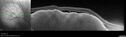

51 year old female with metastatic breast cancer to her bone and brain. She was told about a month ago that there were tumors in her eye. Her vision in the right eye has been declining for a few weeks. VA 20/63 OD, 20/32 OS Her choroidal lesions did not shrink with systemic therapy so in April 2021, she had external beam radiation x 15 sessions and the tumors shrank (4th and 5th set of images)

Bilateral Choroidal Tumors - Metastatic Breast Cancer286 views51 year old female. First 3 sets of images show lesions growing despite systemic chemotherapy. She eventually had external beam radiation x 15 sessions and the tumors shrunk in the last two sets of images00000